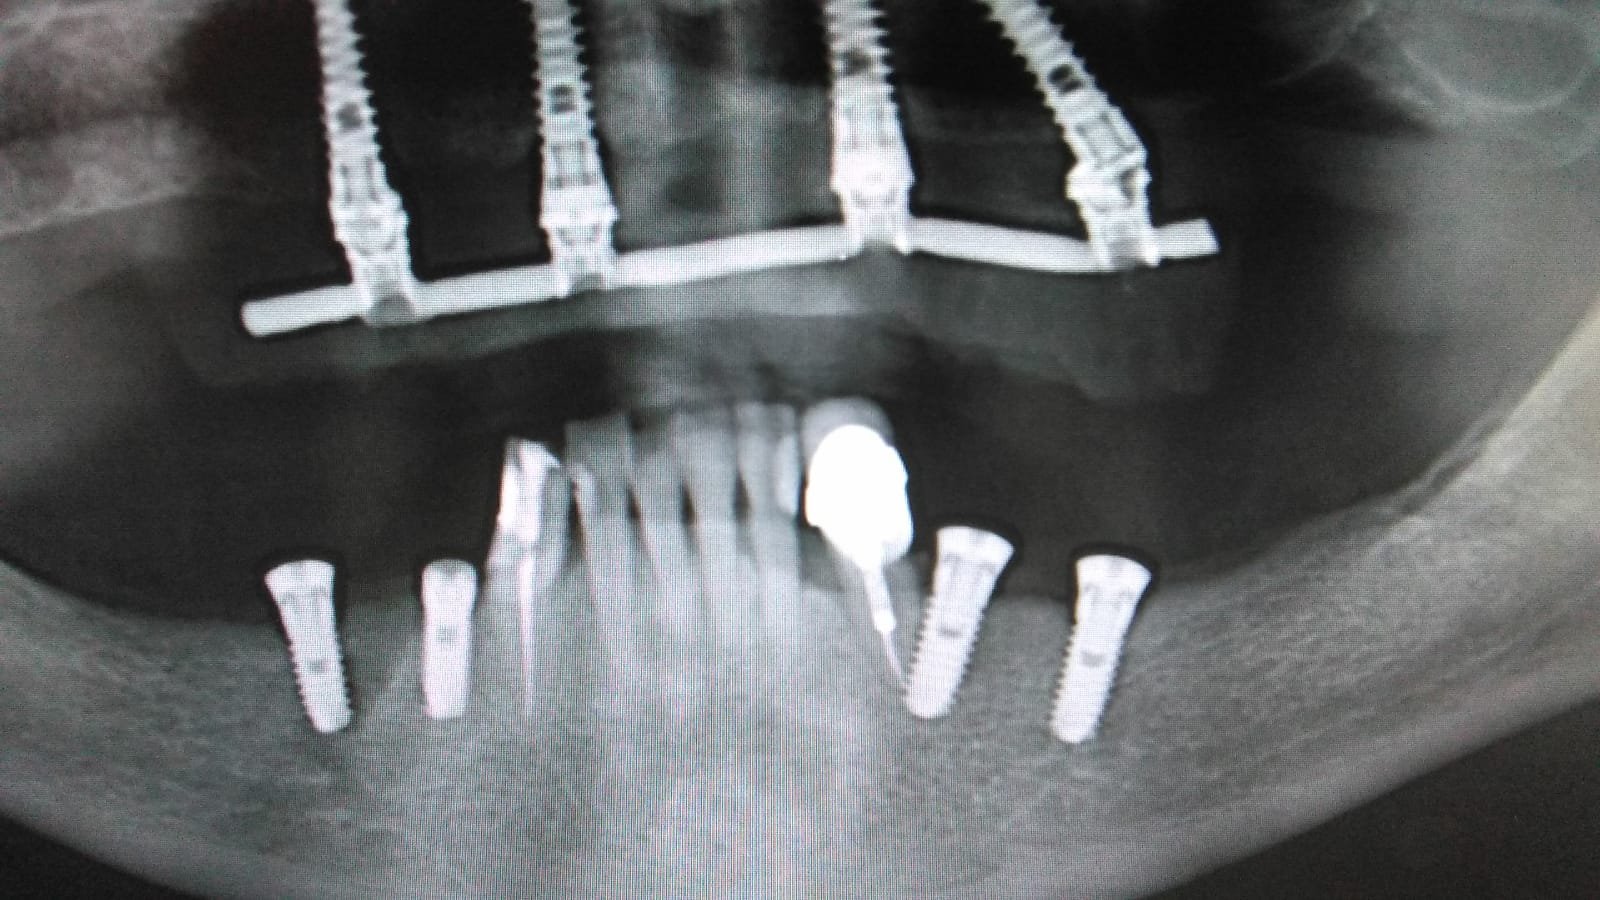

Implante colocado hace más de 15 años en Pamplona en posición 35 (a la izquierda en la rx), con Corona atornillada. Desconozco marca, modelo y conexión. Se necesita información para [...]